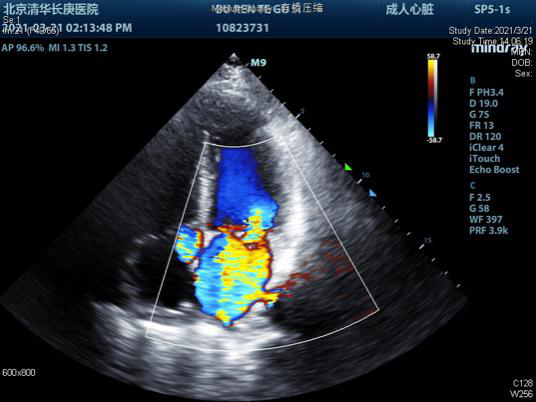

心脏超声显示二尖瓣大量反流

术前超声有二尖瓣大量反流                               崔晓征(左一)与李温斌(右一)为患者手术